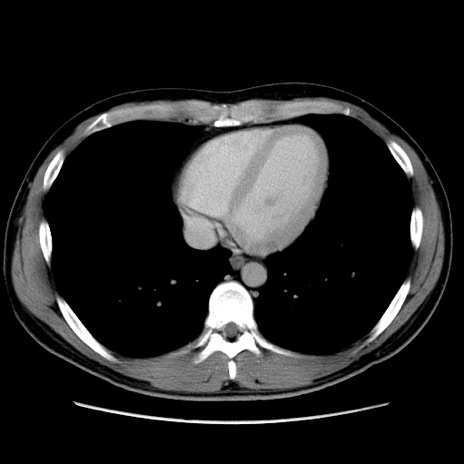

症例36(横断像)

【症例】20歳代 男性

【主訴】心窩部痛

【現病歴】今朝より上腹部痛あり。一旦軽快していたが再度出現したため救急要請。昨日夕に白身の魚を含む刺身を食べた。

【身体所見】BP 136/89mmHg、HR 74/min、BT 37.0℃、腹部:膨満、軟、心窩部に圧痛あり。反跳痛なし、筋性防御なし、腸雑音やや亢進あり。

【データ】WBC 17700、CRP 0.48

冠状断像